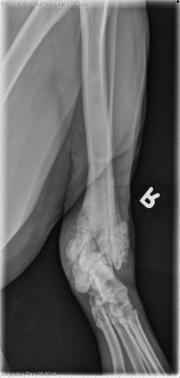

This week’s case is a 2-year-old male neutered Golden Retriever with previous palliative radiation therapy for osteosarcoma. Describe your findings.

Left pelvic limb: There is profuse, irregular new bone formation and destruction of the distal tibia and fibula. There is new bone production cranial to the tarsus as well as caudal to the tarsus. There is a short, oblique, radiolucent line traversing the distal metaphysis and epiphysis of the tibia. Smooth periosteal reaction extends to the mid-diaphysis of the tibia with medullary sclerosis.

• Pathologic fracture of the distal tibial osteosarcoma

• The dense appearance of the tumor is likely secondary to radiation therapy